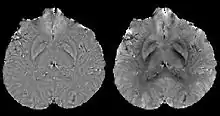

A unique advantage of MRI is that it provides not only the phase image but also the magnitude image. In principle, the contrast change, or equivalently the edge, on a magnitude image arises from the underlying change of tissue type, which is the same cause for the change of susceptibility. This observation is translated into mathematics in MEDI,[13] where edges in a QSM which do not exist in the corresponding magnitude image are sparsified by solving a weighted norm minimization problem.[14]

MEDI has also been validated extensively in phantom, in vitro and ex vivo experiments. In an in vivo human brain, MEDI calculated QSM showed similar results compared to COSMOS without statistically significant difference.[15] MEDI only requires a single angle acquisition, so it is a more practical solution to QSM.